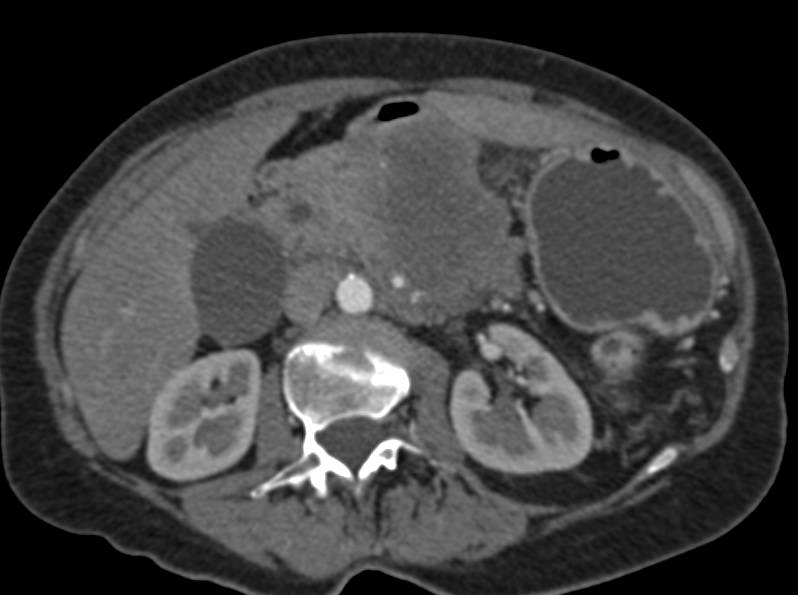

Acute Pancreatitis